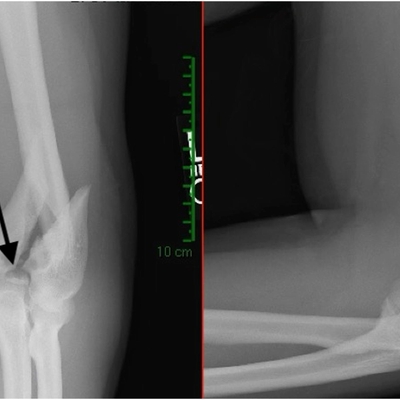

Click on an image below to view more info.